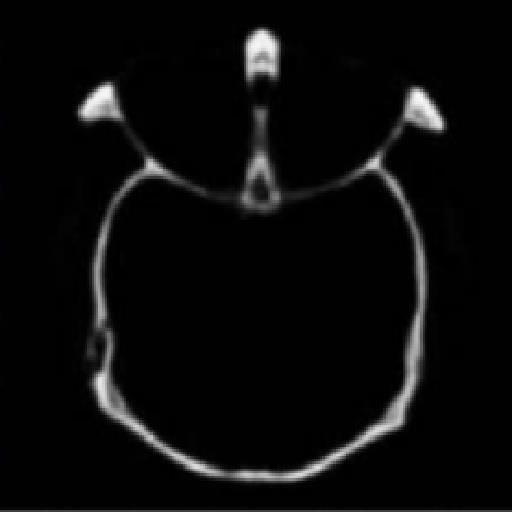

Output

Figure 1: Input image Figure 2: Input image Figure 3: Output image (CT) (MRI) (CT+MRI)